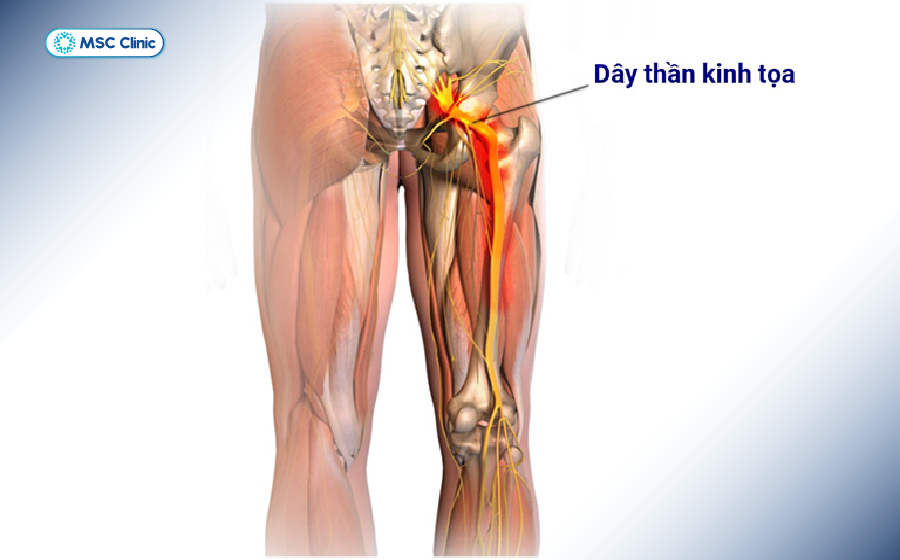

Để trả lời câu hỏi đau thần kinh tọa là gì, chúng ta cần phân tích cấu trúc của dây thần kinh hông to. Đây là dây thần kinh đơn lẻ lớn nhất trong cơ thể con người, có đường kính bằng khoảng một ngón tay cái ở điểm dày nhất.

Dây thần kinh tọa được hình thành từ sự hợp nhất của 5 rễ thần kinh ở cột sống thắt lưng và xương cùng:

- Rễ L4 và L5 (vùng thắt lưng dưới)

- Rễ S1, S2, S3 (vùng xương cùng)

Từ đây, dây thần kinh đi xuyên qua lỗ mẻ hông lớn, chạy dưới cơ hình lê (cơ mông) và kéo dài xuống mặt sau của đùi. Tại vùng khoeo chân (phía sau đầu gối), nó chia thành hai nhánh chính là thần kinh chày và thần kinh mác chung để chi phối cảm giác, vận động cho toàn bộ cẳng chân và bàn chân.

Vị trí dây thần kinh tọa